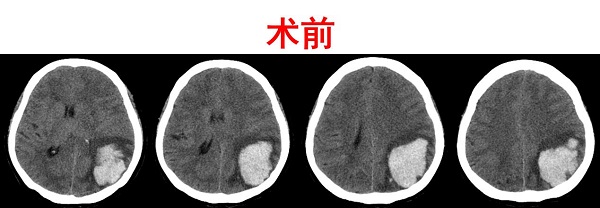

两周前的一个中午,正在打扫卫生的姚阿姨突然感觉到自己的右半边身子“不听使唤”,紧接着就是一阵阵地恶心呕吐,情形十分怪异。焦急万分的家属匆忙将老人送往当地医院检查,随着“脑出血”的诊断结果和转院治疗方案被初步确认,陕健医二一五医院神外重症监护室全体医护立即准备紧急收治,入院后经头颅CT检查发现,姚阿姨“左顶叶脑出血”,出血量达42ml,左侧脑室受压,中线结构移位,并且在查体过程中发现,姚阿姨受病情影响,已经存在混合性失语,右侧肢体严重活动障碍。

姚阿姨年龄较大、病情复杂,如果采用“脑洞大开”的治疗方式,无疑是在挑衅死神。为减少手术创伤,同时达到快速清除血肿的目的,谢国强主任团队选择神经内镜辅助下脑内血肿清除术。以“技术+医术”的双重保障,依据影像数据,科学精准规划手术路径,通过神经内镜的“天眼”,一滴不漏、一丝不伤地将血肿清除,手术时间短、创口小、过程顺利、效果良好。在复查的头颅CT中可以清晰的看到,血肿清除的非常干净。